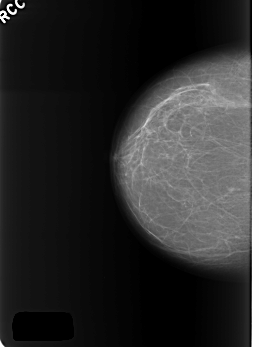

C_0401_1.RIGHT_CC

RIGHT_CC LINES 5552 PIXELS_PER_LINE 4144 BITS_PER_PIXEL 12 RESOLUTION 50 NON_OVERLAY